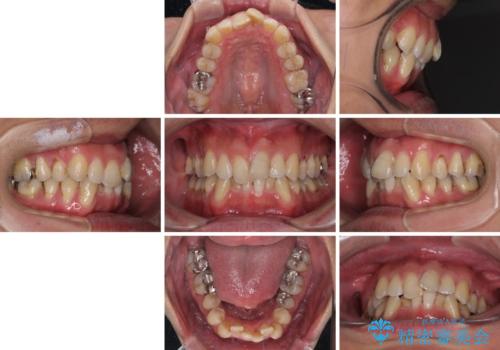

- 前歯のデコボコを気にして来院された患者様です。

下顎前歯のデコボコが特に強く、治療を早く終えることを考えるとワイヤー装置がお勧めですが、ワイヤー装置の異物感は避けたいのでインビザラインを希望されていました。

インビザラインで治療を行うか、ワイヤーで治療を行うかずっと悩んでいらっしゃいましたが、早く終わらせることを優先してワイヤー装置にて治療を行うこととしました。